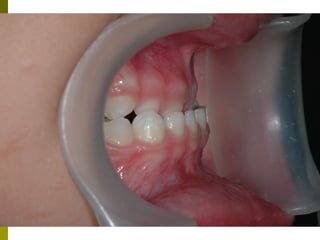

Οδοντικό τραύμα στα πρόσθια δόντια

 Όσο μικρότερο το παιδί, τόσο οι

πιθανότητες για βλάβη στο σπέρμα του

μόνιμου δοντιού είναι μεγαλύτερες

 Συχνότερα σε εμβυθίσεις, ολικές

εκγομφώσεις.